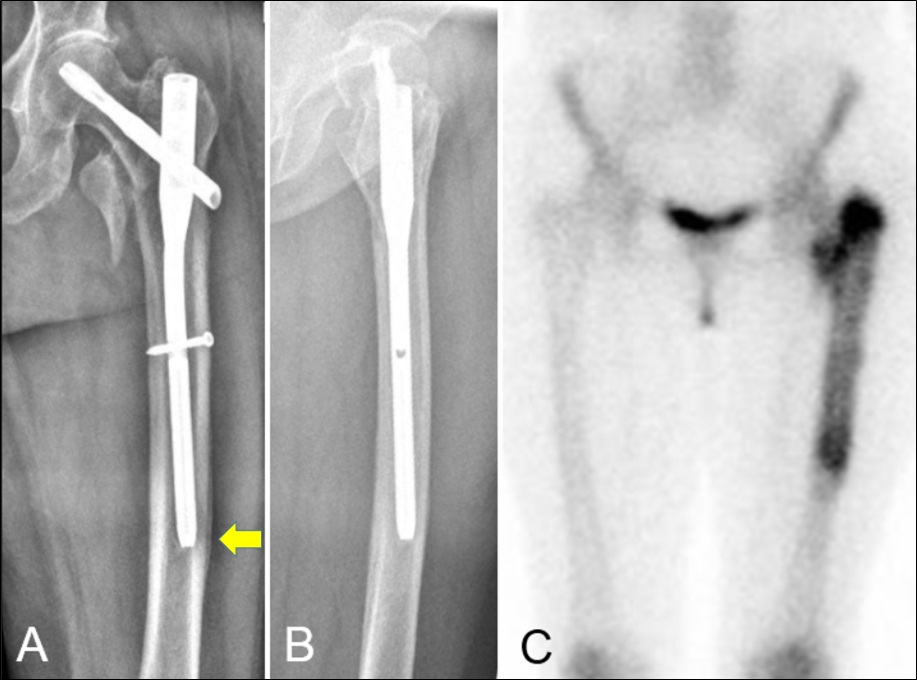

Penetración de la cortical anterolateral en fracturas de fémur proximal tratadas con clavos endomedulares cortos Reporte de dos casos. [Penetration of anterior-lateral cortex in proximal femur fractures treated with short intramedullary nails Report of two cases].